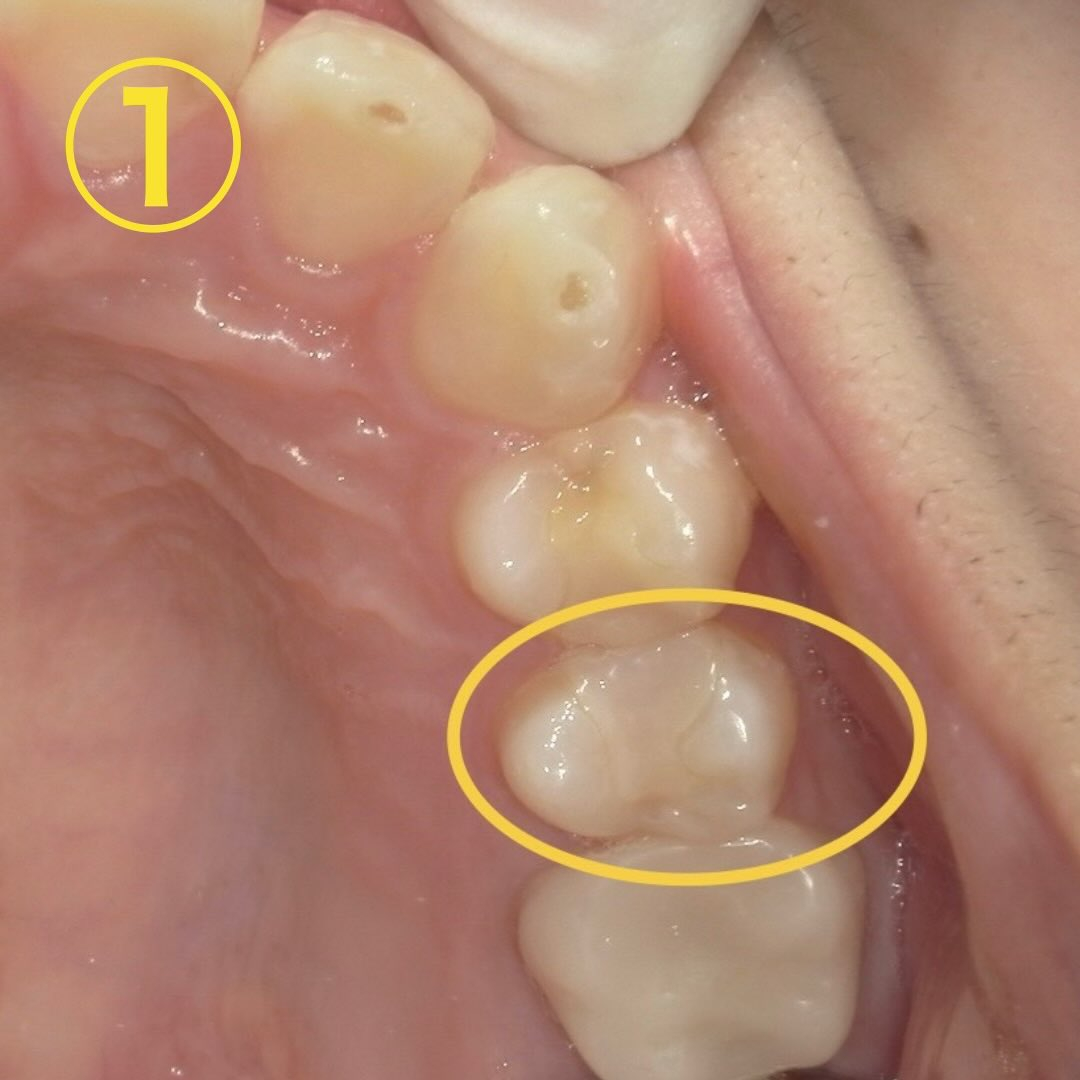

初診時の口腔内写真をお見せします📷

黄色丸で囲った部分が沁みるとの事でした。→画像①

写真を見ると白い詰め物がされているのが分かります🧐

パッと見、穴が空いていたり黒くなっていたりと虫歯の所見は無さそうですが…